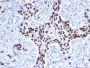

The specificity of this monoclonal antibody to its intended target was validated by HuProt™ Array, containing more than 19, 000, full-length human proteins. Recognizes a 53 kDa protein, which is identified as p53 suppressor gene product. It reacts with the mutant as well as the wild form of p53. It is a tumor suppressor protein expressed in a wide variety of tissue types and is involved in regulating cell growth, replication, and apoptosis. It binds to MDM2, SV40 T antigen and human papilloma virus E6 protein. Positive nuclear staining with p53 antibody has been reported to be a negative prognostic factor in breast, lung, colorectal, and urothelial carcinoma. Anti-p53 positivity has also been used to differentiate uterine serous carcinoma from endometrioid carcinoma as well as to detect intratubular germ cell neoplasia. Mutations involving p53 are found in many malignant tumors, including breast, ovarian, bladder, colon, lung, and melanoma.Primary antibodies are available purified, or with a selection of fluorescent CF® Dyes and other labels. CF® Dyes offer exceptional brightness and photostability. Note: Conjugates of blue fluorescent dyes like CF®405S and CF®405M are not recommended for detecting low abundance targets, because blue dyes have lower fluorescence and can give higher non-specific background than other dye colors.

Positive Control

MDA-MB-231 Cells. Breast or Colon carcinoma

Antibody application notes

Higher concentration may be required for direct detection using primary antibody conjugates than for indirect detection with secondary antibody|Immunohistology (formalin): 0.5-1.0 ug/mL for 30 minutes at RT|Staining of formalin-fixed tissues requires boiling tissue sections in 10 mM citrate buffer, pH 6.0, for 10-20 minutes followed by cooling at RT for 20 minutes|Optimal dilution for a specific application should be determined by user